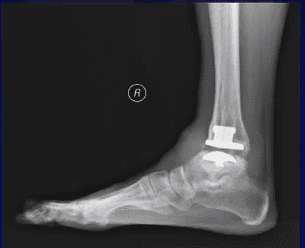

Imaging studies are important tools in diagnosis, therapeutic decision-making, and evaluation of functional results in the area of ankle and foot performance. The most commonly used resources are conventional X-rays with load, ultrasound, computed tomography (CT), and magnetic resonance imaging (MRI). The initial diagnostic investigation often uses conventional X-rays with load to reproduce the three-dimensional bone relationships in the ankle and foot more accurately. However, the information acquired from this method can be limited.

Computed tomography (CT) provides for high-resolution images of the ankle and foot in different axes. Fractures, degenerative changes, bone healing, surgical planning for osteotomies, arthrodeses, and arthroplasties are all instances in which CT is the go-to imaging tool. However, it’s not a perfect option. One distinct issue with conventional CT is the fact that the technology cannot reproduce images of feet and ankles experiencing body weight load.

Over the last ten years, the cone beam computed tomography with load technique (WBCT) proved feasible for the instances mentioned above. It also offers high reproducibility of the real situation of the ankle and foot when body weight is factored in.

This review concluded that WBCT imaging allows correct evaluation of foot and ankle anatomy with the patient in a standing position, providing images with high spatial resolution, short image acquisition time, low dose of radiation, and costs which are similar to other available imaging technologies. This diagnostic tool can be used for decision making in the treatment of deformities of the ankle, hindfoot, midfoot, and forefoot.